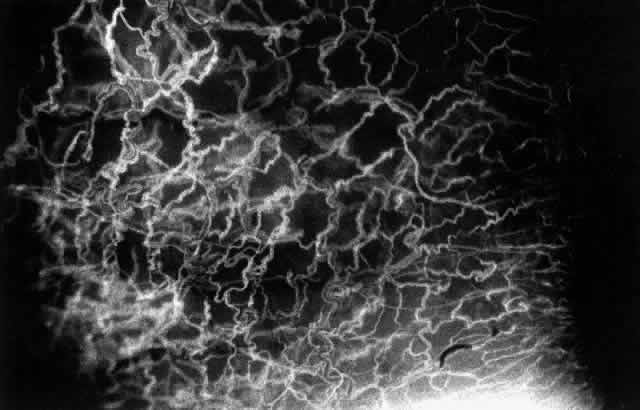

The characteristic features of necrotizing scleritis on fluorescein angiography are hypoperfusion and, eventually, nonperfusion of the vascular networks (Figs. 40 through 43).26 The initial changes are on the venous side of the capillary network; the transit time of the dye increases even if the eye is red and congested. If the disease process persists or has been present for a long time, thrombosis and permanent vaso-occlusive changes occur. These vessels (or the occluded capillary network) are bypassed by the opening of anastomotic channels. New vessels in a granuloma give rise to deep intrascleral leakage of dye (see Fig. 43). Conjunctival and episcleral involvement by the destructive change is late but is always preceded by vaso-occlusive changes that can sometimes be detected with use of the red-free light on the slit lamp (Figs. 44 and 45).